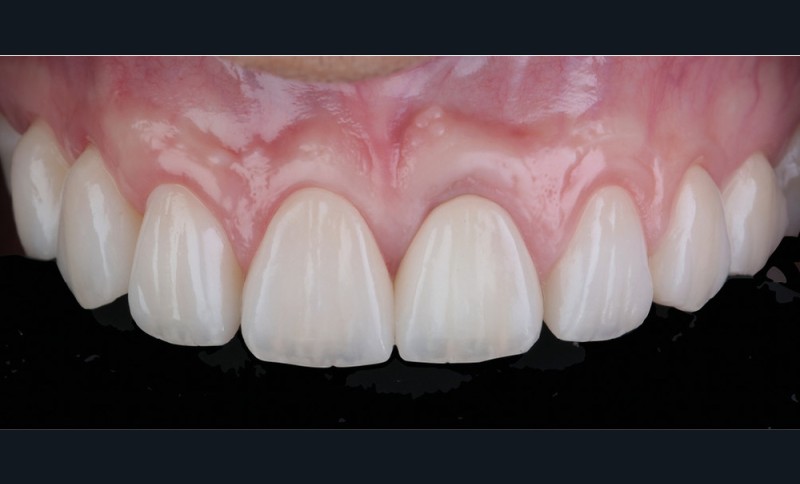

Acte 6 : assemblage et résultat (fig. 9 et 10)

Nous assemblons les céramiques selon la technique choisie (scellement pour les couronnes et collage pour les facettes). Le patient est revu à quinze jours pour contrôle de la cicatrisation.